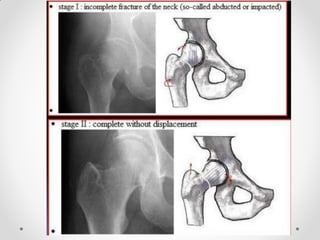

Plain radiograph

• Shenton’s line disruption (continuous line from medial edge of

femoral neck and inferior edge of the superior pubic ramus)

• lesser trochanter is more prominent due to external rotation

of femur

• femur often positioned in flexion and external rotation (due to

unopposed iliopsoas)

• asymmetry of lateral femoral neck/head

• sclerosis in fracture plane

• smudgy sclerosis from impaction

• bone trabeculae angulated

• nondisplaced fractures may be subtle on x-ray

Shenton’s line